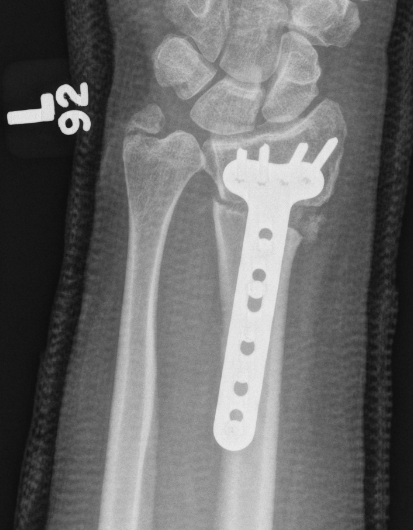

Ulnar Shortening

Indications

Short radius, positive ulna variance

Acceptable alignment distal radius

Acceptable DRUJ

Technique

Approach to ulna

- between ECU and FCU

- can use cutting jigs

- resect 2 - 6 mm of ulna based on xray templating

- compression plate